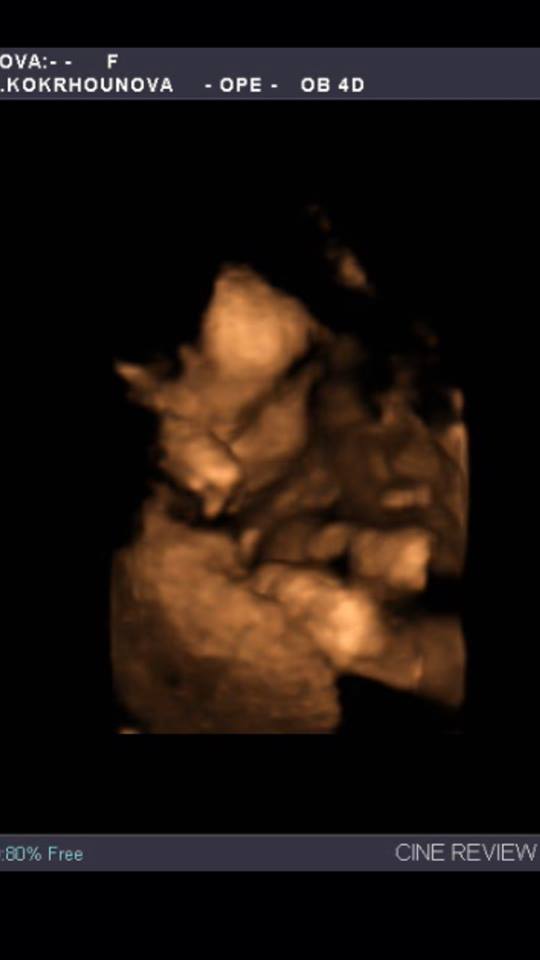

Teda když koukám na ty fotky z UZ tak musím uznat, že já měla štěstí 🙂 a prtě se hezky ukázalo 🙂 🙂 ... od začátku nám tvrdí, že to bude holčička tak budu doufat že tomu tak i bude 🙂 příští týden mě čeká velký UZ na kterém se to pokud to dobře půjde i prý potvrdí.... tak jsem zvědavá.... první fotka je z cca 10týdne ta druhá je měsíc stará.... 🙂 ale i tak než to vykoukne na svět tak člověk jistotu stejně nemá 🙂 🙂